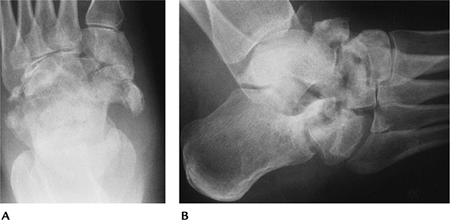

FIGURE 6-20 AP (A) and lateral (B)

radiographs demonstrating severe posttraumatic arthritis with osseous fragments in the joint and marked tibiotalar joint asymmetry. |